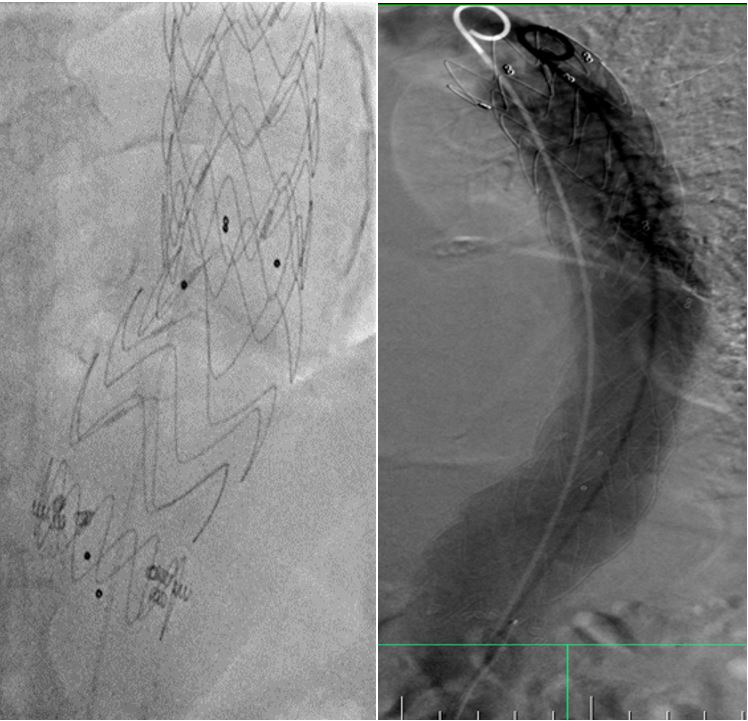

Pacient s objemnou výduťou hrudnej aorty s krátkou implantačnou zónou ošetrený za pomoci 3D navigácie hrudným stentgraftom a fixovaný pomocou endoskrutiek za účelom zabránenia neskorej migrácie (posunu) graftu.